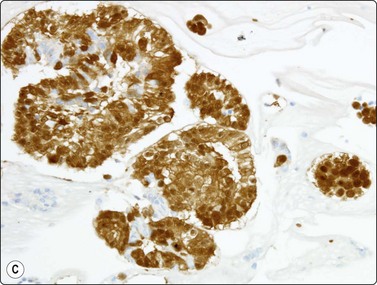

Fig. 8.24 Primary adenocarcinoma

Strong positive nuclear staining for TTF-1 (Cell block, IPOX, HP).

There are no absolute cytological criteria for separating primary from secondary adenocarcinomas, although there may be features indicative of a particular organ of origin (see Chapter 5). Immunostaining for TTF-1 provides the best single marker of a primary origin (Fig. 8.24), although it should be recognised that metastic thyroid malignancies and occasionally metastases from other sites may be TTF-1 positive.144-146